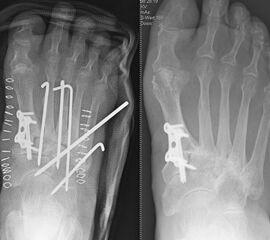

Degenerative Veränderungen zeigen sich am häufigsten im Bereich der Tarsometatarsalgelenke I-III-Gelenke 21. Hier kommt typischerweise eine Stabilisierung der medialen Säule mittels  Lapidusarthrodese und Arthrodese der Tarsometatarsalgelenke II und III in Frage. In seltenen, meist posttraumatischen Fällen ist auch die laterale Säule mit den Tarsometatarsalgelenken IV und V betroffen. Letztlich gilt es präoperativ zu erörtern, welche der Gelenke Lisfranc Gelenkreihe schmerzhaft sind, um diese gezielt versteifen zu können.

Es kommen verschiedene technische Möglichkeiten der operativen Versorgung in Frage.  Verwendung finden vor allem winkelstabile Plattensysteme, Schraubenosteosynthesen, Klammern, intraossäre Nagelsysteme, temporäre Kirschnerdraht-Transfixationen, Einbolzen von trikortikalem Span und Anlagerung von Spongiosa aus dem Beckenkamm oder dem Tibiakopf  (Abb. 2 und 3).

Durch die Arthrodese soll, wie oben beschrieben, eine Schmerzreduktion, eine Wiederherstellung der Fußstabilität und eine Korrektur der Fußstellung erreicht werden. Hierbei gibt es unterschiedliche Ansätze. Einige Autoren versteifen stets die mediale und laterale Säule bei TMT-Arthrosen 22. Andere Autoren sind der Meinung, dass nur die mediale Säule versteift werden sollte 18. Andere wiederum dehnen den Eingriff aus und beziehen die Cuneiforme-Gelenke mit in die Lisfranc-Arthrodese ein 21. Grundsätzlich zeigt sich der Trend, dass nur isoliert die arthrotischen und symptomatischen Gelenke versteift werden, ferner die Zugangswege klein und die Resektionsflächen der einzelnen Gelenke nur bis zur subchondralen Spongiosa eröffnet werden 23.